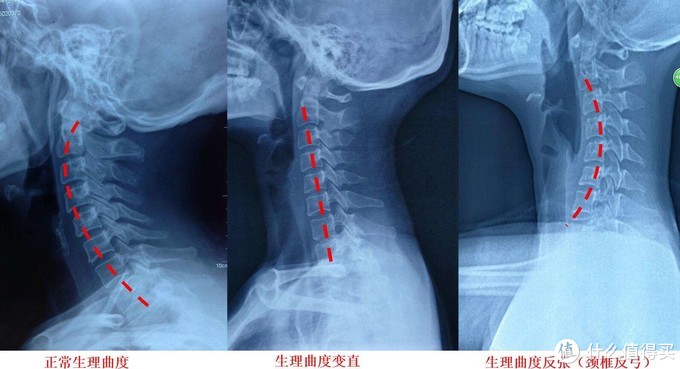

在医学上来说,颈椎指的是我们人体脊椎的第1~7节椎骨,并且包括了穿过其中的脊神经,以及颈椎周围的颈椎肌群。颈椎系统与我们的头部以及胸椎相连,如果只是承托头部而忽视了对颈部及肩部的承托,那么颈椎就会呈现反曲压迫,是的颈椎肌群不能得到放松和修复,久而久之就会形成病理性的颈椎强直,并引发各种颈椎病及衍生病症。而如果只承托颈部,而忽视了对头部及肩部的承托,那么就会导致颈椎过曲,照样会引发问题。

因此,合适的头颈肩承托其实是一体的,只有在每个部位都得到合适的承托时,我们的颈椎才会真正健康。